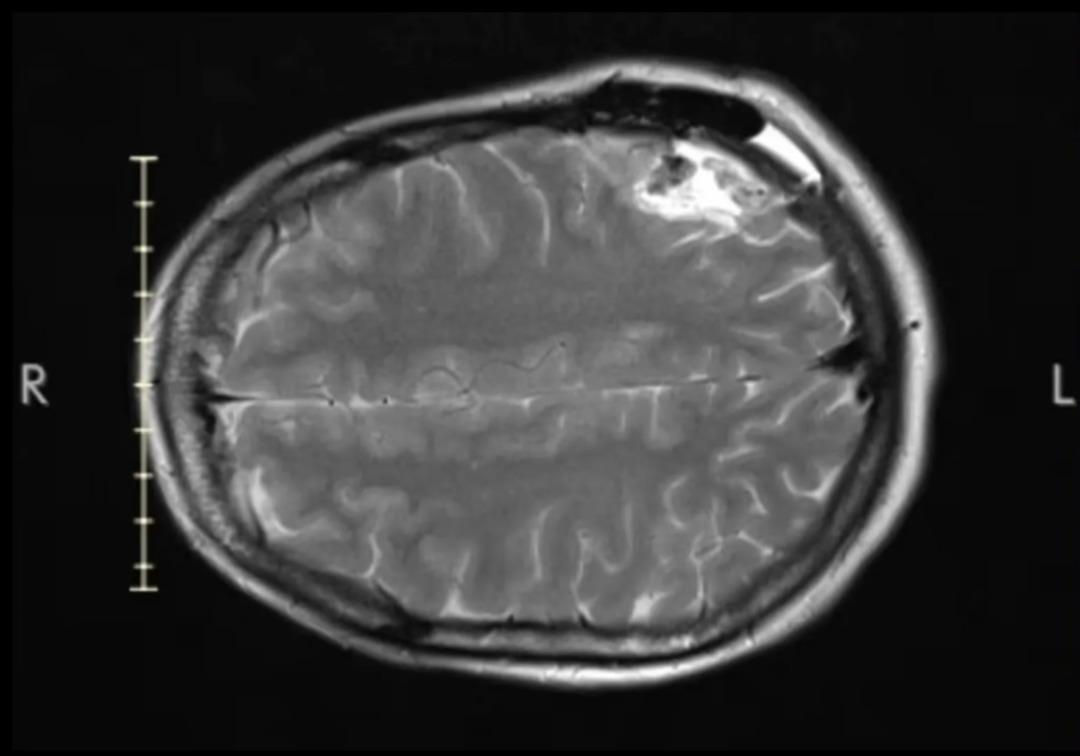

Doktorlar ilk olarak sarsıntı veya omurga kırığı ihtimali üzerinde durdu. Ancak yapılan beyin taramalarında beyninde şüpheli bir gölge tespit edildi.

Yapılan tetkiklerin ardından Macpherson’a nadir görülen bir beyin tümörü olan Oligodendroglioma teşhisi konuldu. Doktorlar ilk etapta genç kadına yalnızca 12 ay ömrü kalmış olabileceğini söyledi.